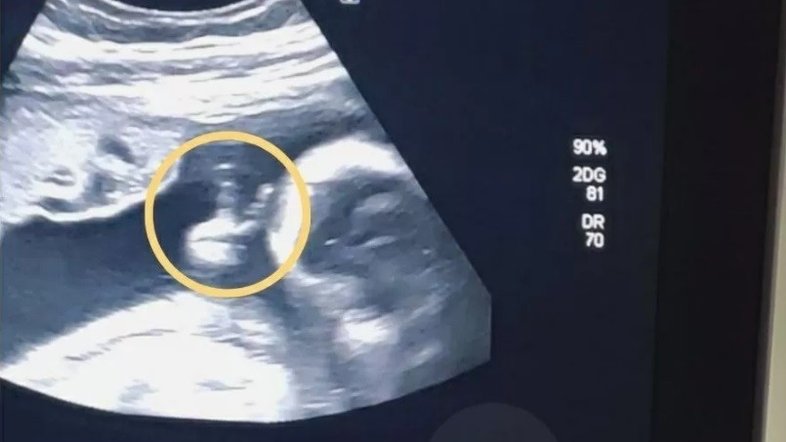

Felipe Moreira dos Santos, de 32 anos, foi surpreendido durante o ultrassom da esposa Camila Ferreira, de 24 anos, com o que pareceu ser um gesto de “V” nos dedos do filho do casal.

Diagnosticado com um câncer que tirou seu rim esquerdo e que depois se espalhou pelo baço, Felipe interpretou o gesto do filho como um sinal de vitória.

“Minha imunidade estava muito baixa por conta da quimioterapia, mas minha esposa insistiu para que eu fosse ao ultrassom. Quando chegamos, comecei a gravar com o celular, eu queria registrar as batidas do coração. De repente a médica avisou ‘olha, ele está fazendo um sinal de V’. Na hora não tive reação”, disse Felipe, em entrevista ao UOL.